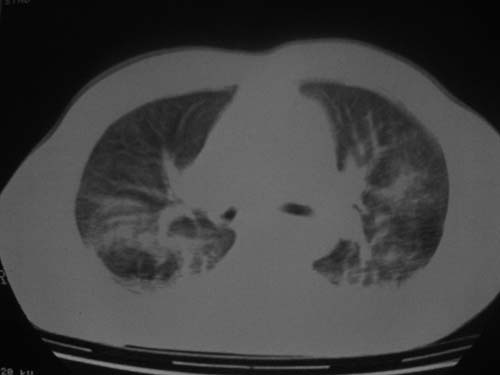

外伤病人,年龄忘了,中年人右侧肋骨骨折了,

这是刚住院拍的片子。